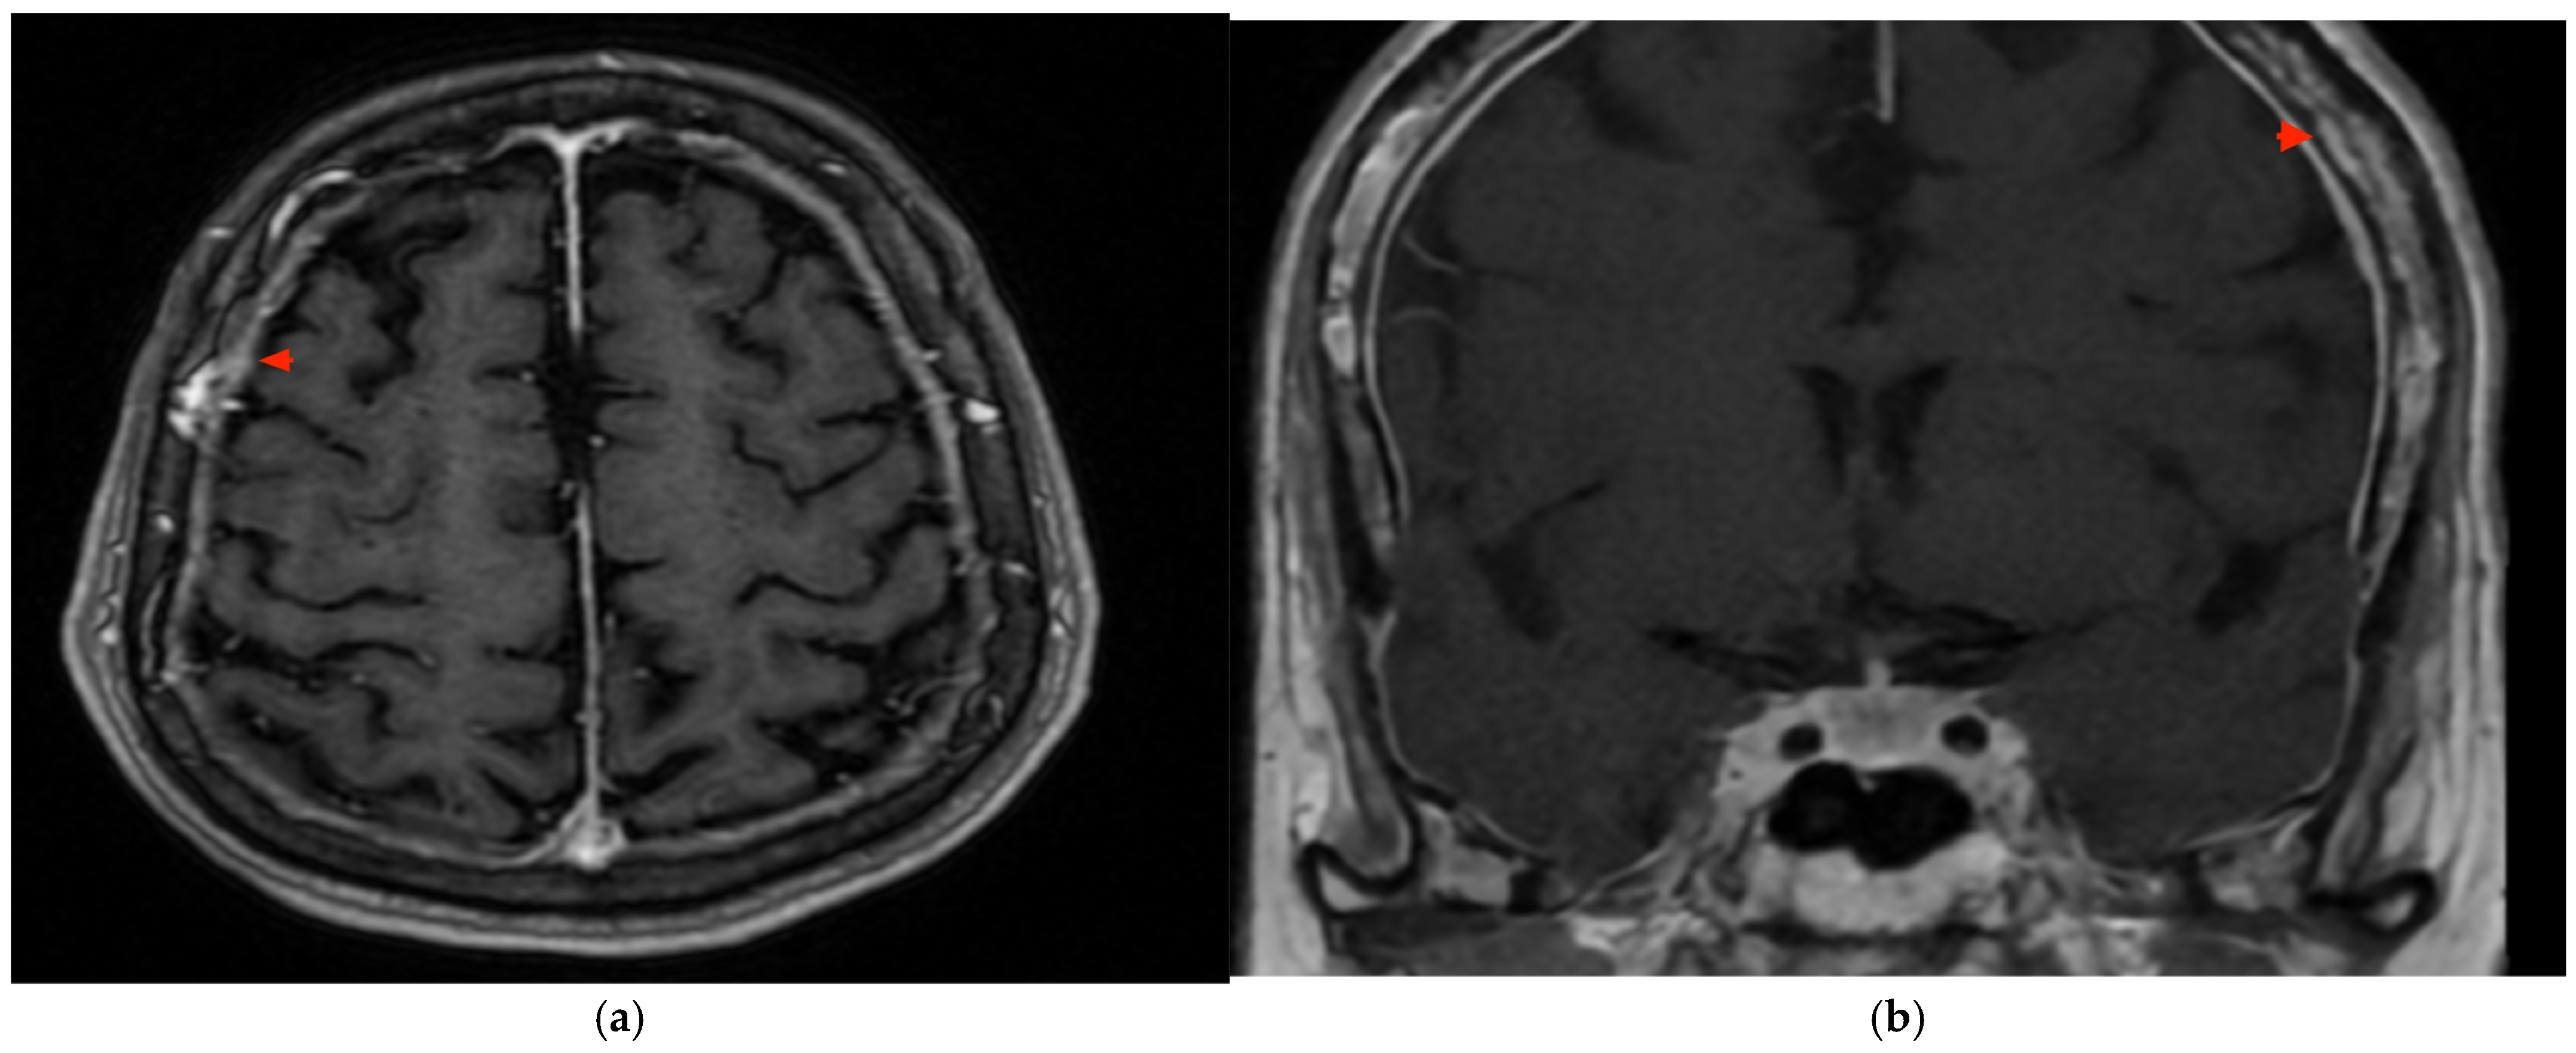

2. Case Presentation